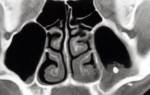

- Пункция. Врач вводит специальную иглу (игла Куликовского) в нижний носовой ход и достигает верхней точки свода. Прокалывать нужно именно здесь, так как толщина костной стенки в этой зоне минимальна. Врач пунктирует боковую стенку гайморовой пазухи и продвигает иглу внутрь последней на 1,2-1,5см. Далее к игле присоединяется шприц, который обеспечивает извлечение содержимого из полости. После пазуху тщательно промывают, вводят антисептик, возможно также антибиотик (на усмотрение лечащего врача).

На рисунке выше изображена процедура пунктирования.